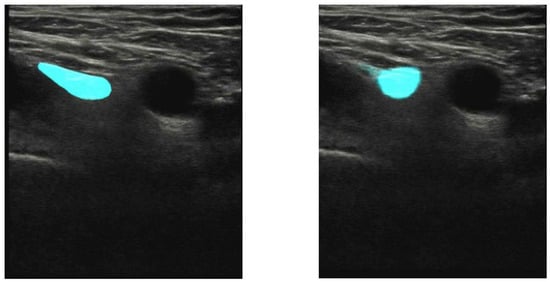

- Bowness, J.; Varsou, O.; Turbitt, L.; Burkett-St Laurent, D. Identifying anatomical structures on ultrasound: Assistive artificial intelligence in ultrasound-guided regional anesthesia. Clin. Anat. 2021, 34, 802–809. [Google Scholar] [CrossRef] [PubMed]

- Bowness, J.; Burckett-St Laurent, D.; Hernandez, N.; Keane, P.A.; Lobo, C.; Margetts, S.; Moka, E.; Pawa, A.; Rosenblatt, M.; Sleep, N.; et al. Assistive artificial intelligence for ultrasound image interpretation in regional anesthesia: An external validation study. Br. J. Anaesth. 2023, 130, 217–225. [Google Scholar] [CrossRef]